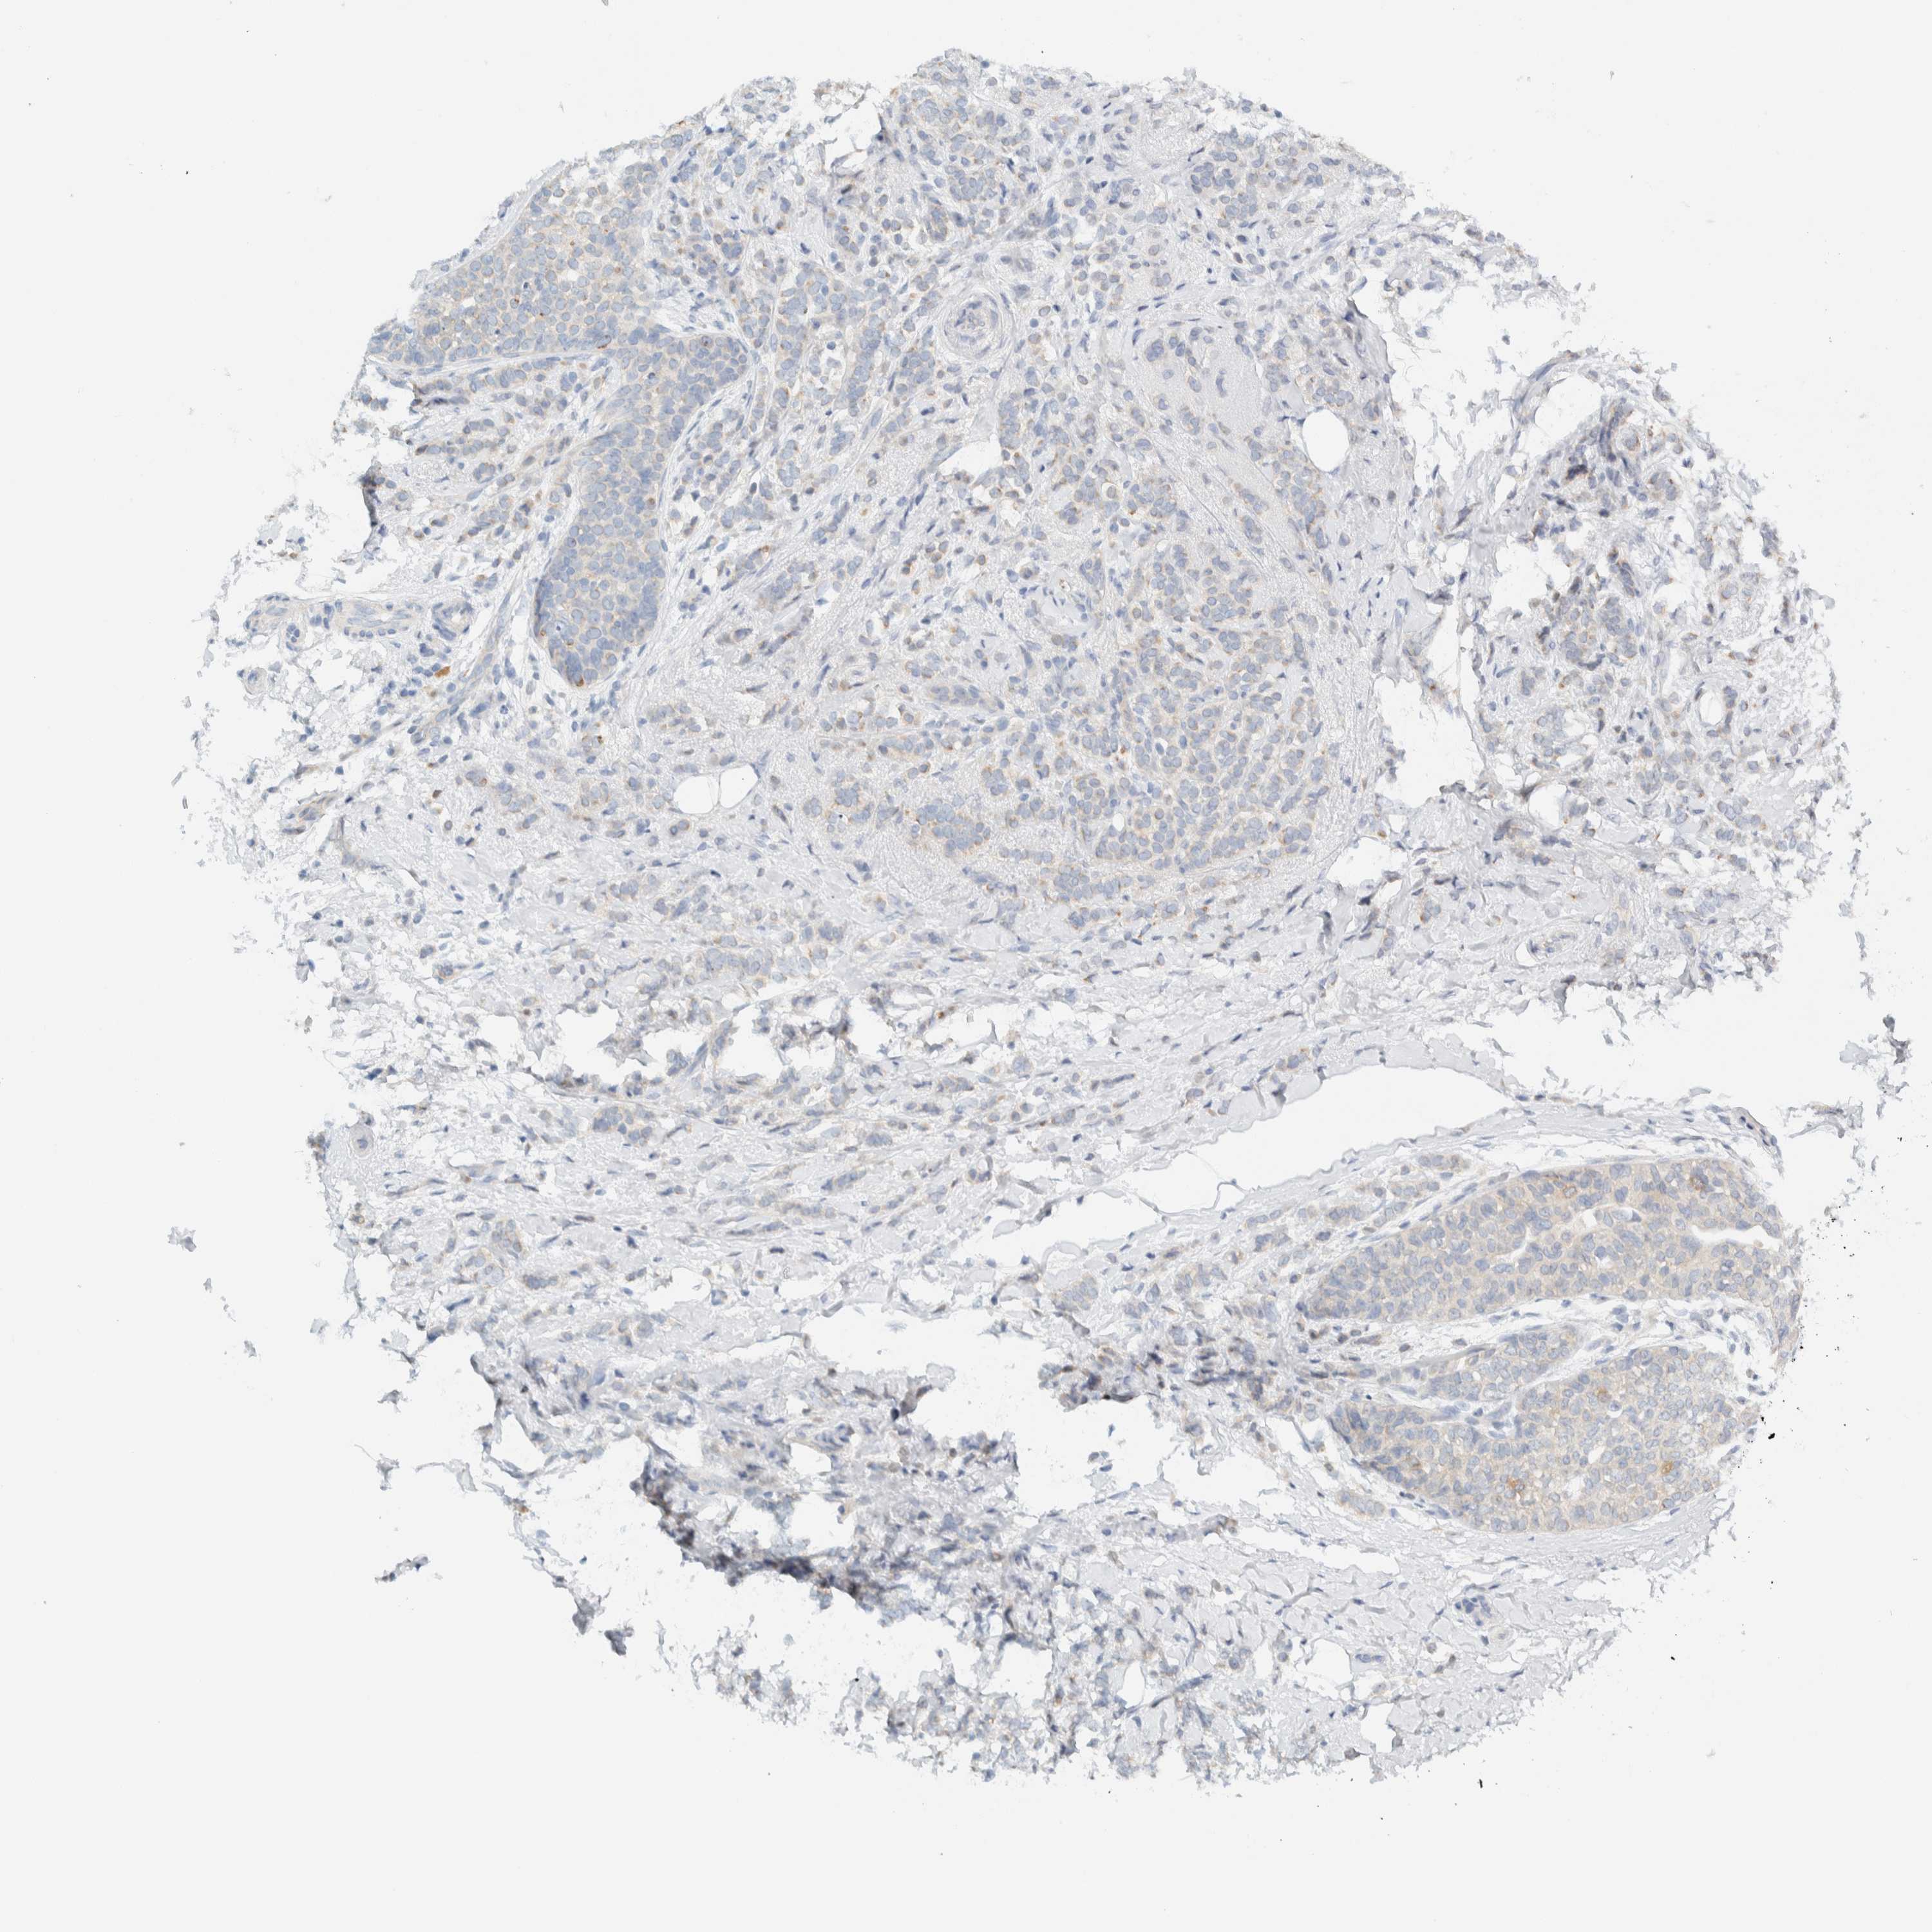

CANCER BREAST CANCER Show tissue menu

BRCA TCGA BRCA VALIDATION PROTEIN EXPRESSION